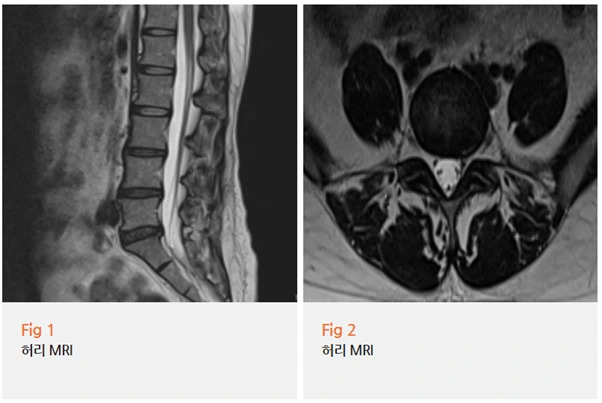

결과를 보는 순간... 역시나였습니다.

L4-L5 레벨에서 추간판 탈출증이 명확하게 보였어요.

그것도 왼쪽으로 돌출되어 신경근을 압박하고 있었죠.

환자분 증상이 좌측 종아리 통증이었던 이유가 바로 이거였어요.

환자분께 영상을 보여드리면서 설명드렸습니다.

여기 이 부분이 신경을 누르고 있고,

이 신경이 바로 종아리 바깥쪽으로 내려가는 신경이에요.